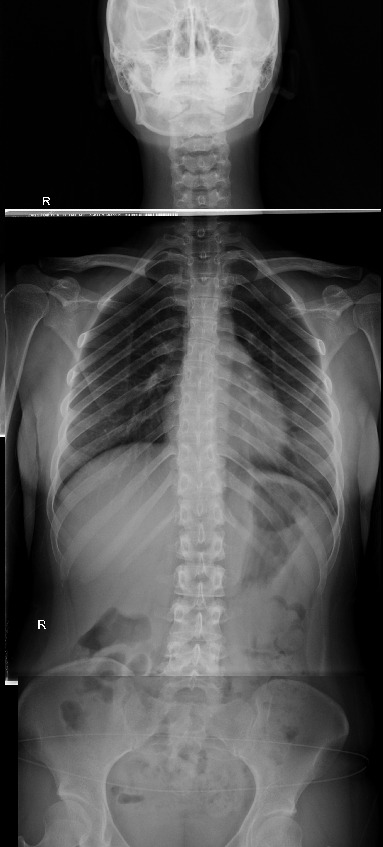

23살 여성

우측 경골이 2.5cm 더  길다. 그 결과로 골반, 척추의 측만증이 발생함.

2. 우측골반 상승

3. 천골이 nutation, 틀어짐.

요추가 좌측회전, 측만발생

4. 요추 과전만, sacral angle증가

5. 경추 reverse curve

- 거의 모든 측만증에서 경추는 일자목 or reverse curve임.